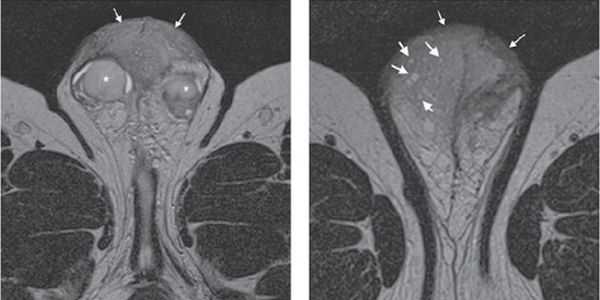

При проведении ультразвукового исследования полового члена олеогранулёма сканируется как гипоэхогенное (меньше й плотности) скопление овальной или неправильной формы, располагающееся в толще подкожных фасций полового члена или интракавернозно (внутри пещеристых тел). Данный метод диагностики направлен на определение границ и распространённости патологического процесса в зонах заинтересованности (половой член, мошонка, лобковая зона и зона промежности), а также на исключение патологической масляной субстанции в кавернозных телах.

В некоторых случаях допустимо выполнение магнитно-резонансной томографии (МРТ) Оно выполняется при более углублённом обследовании, а также в случаях, когда ультразвуковое исследование малоинформативно. МРТ позволяет визуализировать окружающие наружные половые органы мужчины и ткани (кости, мягкие ткани, нервы, сосуды и многое другое).